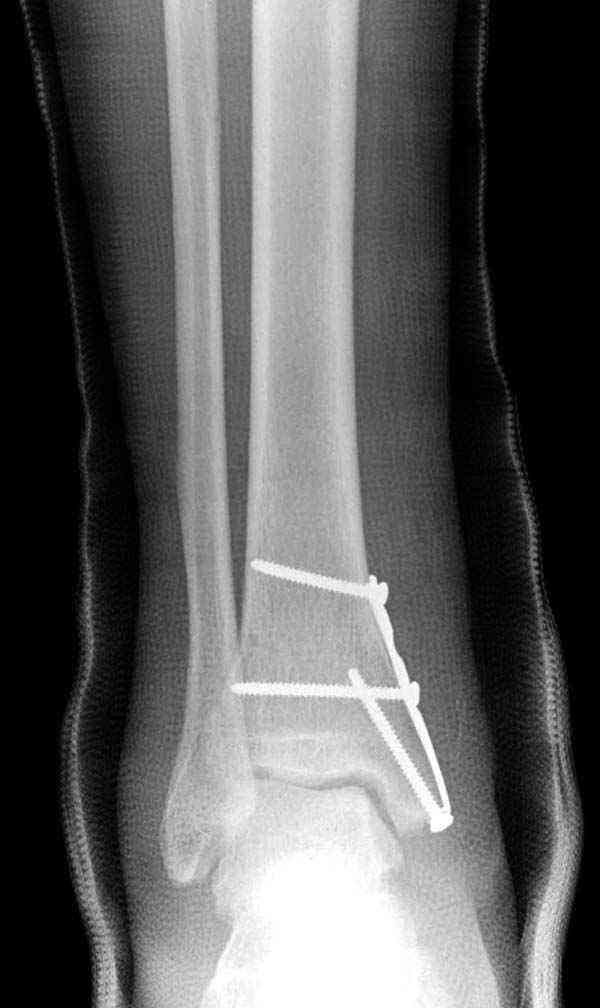

Описанная вами техника "Внутренняя лодыжка фиксирована по Веберу, наружная реконструктивной пластиной с наложением болта-стяжки" существует, но этот подход морально устарел, и применяется очень редко, только при отсутствии имплантов.

Реконструкционные пластины на лодыжке очень грубые, и из-за тонкого слоя кожи над дистальным концом малоберцовой могут осложниться пролежнями кожи изнутри.

Нет первичных снимков, перелом очень низкий и под большим сомнением диагноз разрыва синдесмоза. Медиальная сторона отрепонирована на "хорошо" и, по-видимому, прорезание проволоки произошло во время операции. Без снимков трудно судить о высоте малоберцовой, а лодыжка находится в варусе. Лагирование получилось, но возле тонких шурупов передне-задний шуруп выглядит немного тяжеловато.

Во всех руководствах АО имеется описание техники применения низкопрофильных пластин 1/3 трубки, которые могут быть применены для фиксации наружной лодыжки. Фиксацию проводят кортикальными 3.5 мм шурупами, и если дистальная фиксация недостаточная, тогда усиливают конструкцию созданием hook plate. Сгибая конец пластины на последнем отверстии, внедряют его в дистальный отдел, и тем самым создается дополнительная фиксация.

Современные преконтурированные пластины не имеют таких недостатков, и разделяются на правые и левые, а также на латеральные и задние. Множественные дистальные шурупы 2.7 мм уменьшают подкожное раздражение, и такой имплант можно оставить на долгий срок без удаления.

Для молодых достаточным бывает обычная лодыжечная пластина без блокировки, и только у пожилых с остеопорозом лучше взять полиаксиальные пластины с угловой стабильностью.

Здесь несколько частных случаев: перелом голеностопа со сравнительными снимками и разрыв синдесмоза, а также медиальная Hook пластина.